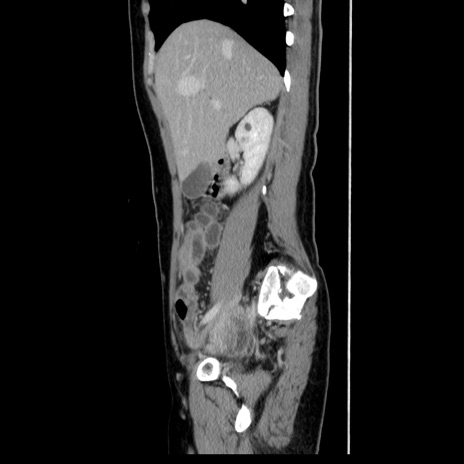

症例39(矢状断像)

【症例】40歳代女性

【主訴】上下腹部痛

【現病歴】2日目から下腹部痛あり。夜間は痛みで眠れなかった。昨日より上腹部痛と下痢が出現。臥位で痛みは軽快したため、休んでいた。本日になって臥位でも立位でも痛みが強くなってきたため救急要請。

【既往歴】子宮内膜症

【身体所見】部:平坦・軟、左上下腹部に圧痛あり、反跳痛あり。

【データ】WBC 21800、CRP 26.78

CT